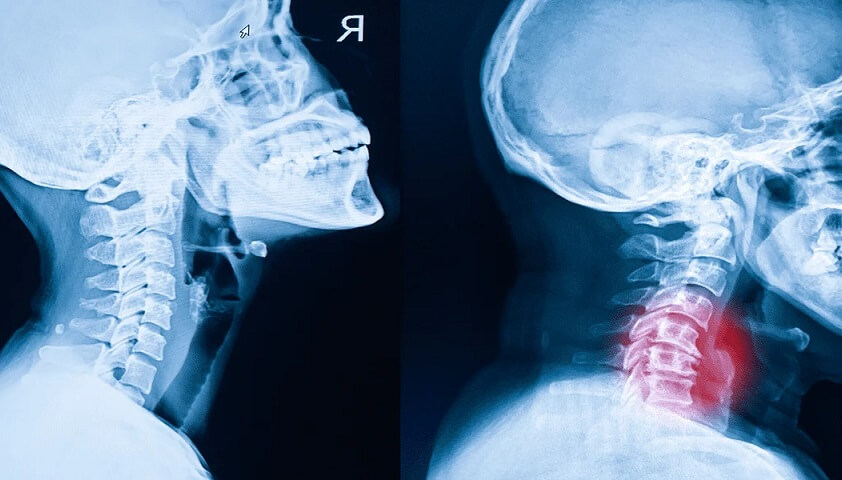

ستون فقرات ما در ناحیه گردن از ۷ مهره کوچک تشکیل شده است. بین این مهره ها، دیسک هایی وجود دارند که مثل کمک فنر عمل می کنند. با افزایش سن یا وارد آمدن فشارهای غیر اصولی، این دیسک ها آب خود را از دست می دهند و نازک می شوند. در نتیجه، مهره ها به هم نزدیک تر شده و ممکن است روی هم ساییده شوند. بدن برای جبران این وضعیت، شروع به ساختن استخوان های اضافه به نام “خار استخوانی” یا اوستئوفیت می کند که همین خارها عامل اصلی درد و فشار بر اعصاب هستند.

اسپوندیلوز گردنی یک اصطلاح کلی برای فرسایش ناشی از سن است که دیسک های ستون فقرات در گردن شما را تحت تاثیر قرار می دهد. با کاهش آب و کوچک شدن دیسک ها، نشانه های آرتروز ظاهر می شوند